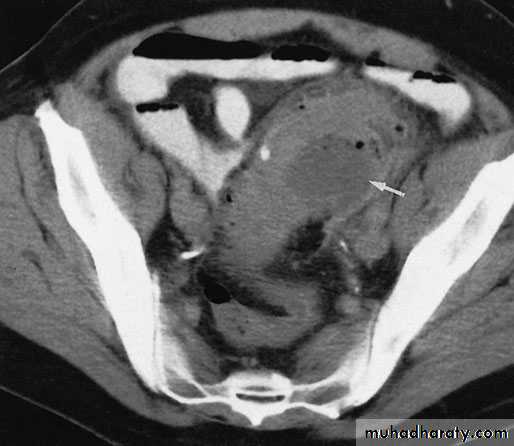

Computerized tomography scan showing a segment of thickened sigmoid colon with a paracolic abscess (arrow) in a patient with diverticulitis.

This will demonstrate not only the diverticula but also any associated pericolic abscess .Barium enemas & sigmoidoscopy are usually reserved for patients who have recovered from an attack of acute diverticulitis, for fear of causing perforation or peritonitis.